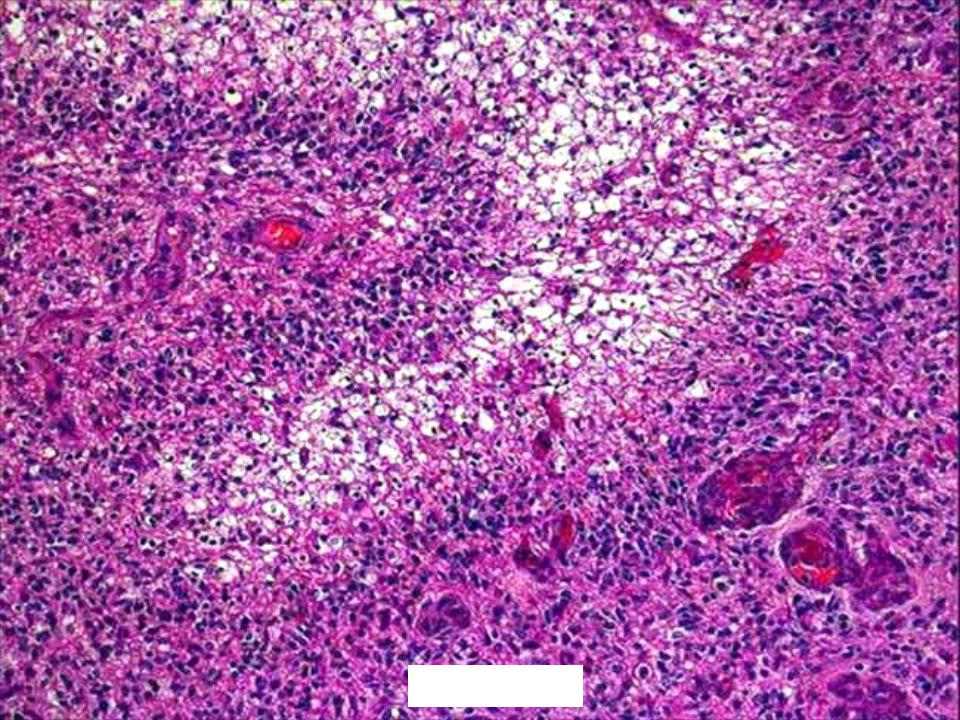

Микрофотографии гистологии глиобластомы головного мозга